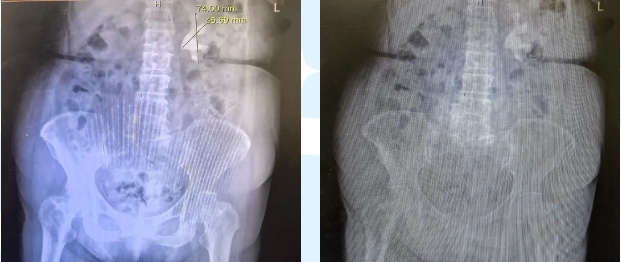

张老太术前拍片

术前准备:术前需进行详细的检查,包括血常规、尿常规、肾功能、影像学检查(如CT、B超等),以确定结石的位置和大小。同时,患者需禁食、禁水6-8小时。